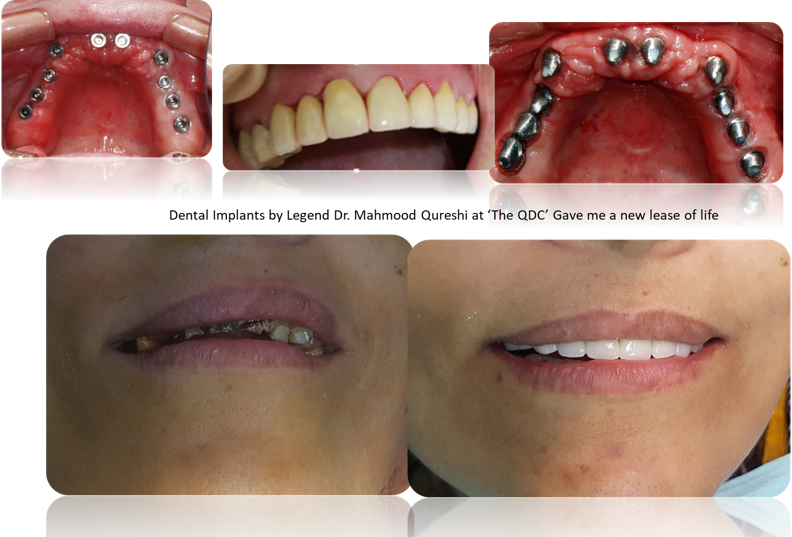

Unveiling the Artistry of Dental Implants at

“The QDC

At the “QDC”, our signature atraumatic technique redefines the experience of dental implant placement, ensuring flawless painlessness while seamlessly blending simplicity with unparalleled precision and comfort.

This exclusive, cutting-edge approach stands as a true masterpiece of innovation, thoughtfully envisioned and meticulously perfected by the renowned Implant Icon, Dr. Mahmood Qureshi (Dr. MQ).

The fusion of talent and expertise at Qureshi Dental Centers has redefined innovation and excellence in dentistry. Dr. Qureshi’s visionary techniques and mastery in dental aesthetics have transformed countless lives and set new benchmarks in implant surgery.